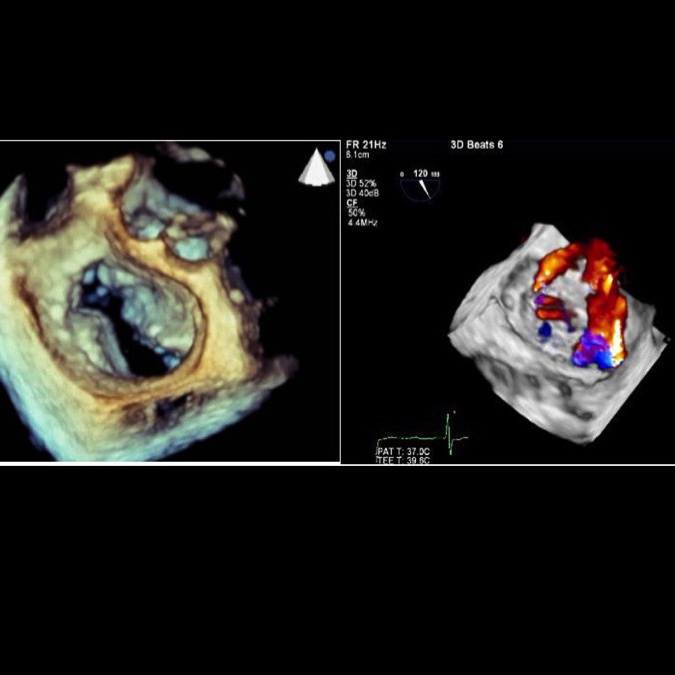

リアルタイム3Dエコー

人間の体はもとより3次元的なものですから、2次元の情報のみで評価することには限界があります。それを克服するする手段としてリアルタイム3次元心エコー図法が開発され臨床的にも用いられています(図3)。